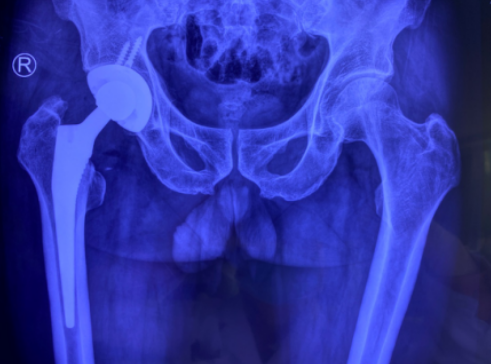

术前

关节科邱东新副主任医师给许大爷作了仔细检查,建议手术,因为像许大爷这样的情形,手术越早开展,术后的并发症就越少。对于许大爷家人“老人这么大年纪了,这么大的手术,身体能不能吃得消,能不能承受的问题”,邱医生给他们讲,首先这种骨折是必须手术的,不手术带来的后果会更严重,后期长期卧床不能活动会带来血栓、肺炎、褥疮等多种风险,医学统计有30%的患者会在半年内死亡。其次,髋关节置换手术,这个普通人眼中的大手术,对于关节科医生来说,只是一个常规手术,经过邱东新医生团队的优化处理,已经可以做到无需插尿管,无需插引流管,也无需输血,手术时间也就一小时半左右,所以手术的风险也降到了最低,术后能够达到快速康复,很快就能恢复正常生活状态。讲明利弊后,许大爷及家人都同意进行手术。

术后

完善相关检查后,邱东新副主任医师团队联合麻醉科会诊,制定了最优化的麻醉及手术方案,保证手术细节的完善周全。随后,手术团队给许大爷进行了右人工全髋关节置换术,手术进行了1个半小时,顺利完成。术后,老人被送回关节病区康复。此后,老人的康复速度很快,第2天就下床在助行器帮助下行走,第3天就不用助行器行走了,术后5天出院。